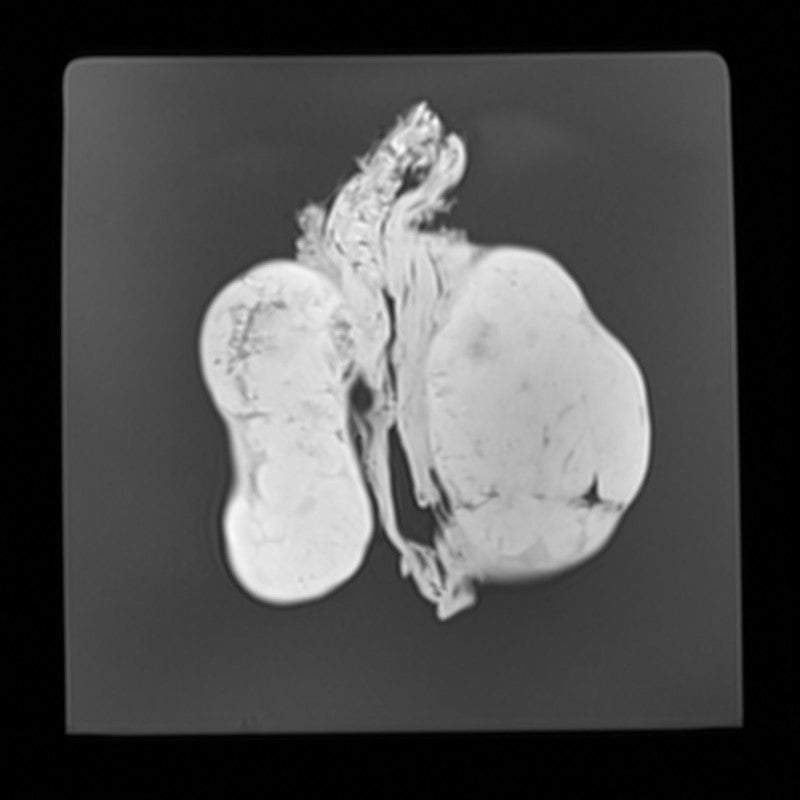

Kidney - Nephroblastoma